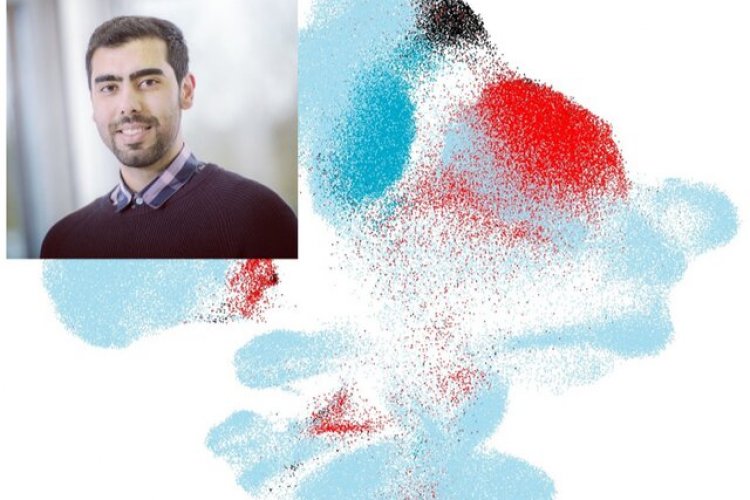

پژوهشگران "دانشگاه فنی مونیخ"(TUM) به سرپرستی "محمد لطفالهی"(Mohammad Lotfollahi)، دانشمند ایرانی، الگوریتم جدیدی موسوم به "scArches" ابداع کردهاند. بزرگترین مزیت الگوریتم scArches این است که به جای به اشتراک گذاشتن دادههای خام با مراکز درمانی و پژوهشی، از انتقال یادگیری استفاده میکند تا پایگاه دادههای جدید از ژنومیک تکسلولی را با منابع موجود مقایسه کند و بدین ترتیب، حریم شخصی و ناشناس ماندن نیز حفظ شود. این کار موجب میشود که تفسیر دادههای جدید نیز به سادگی صورت بگیرد.

پژوهشگران از scArches برای بررسی کووید-۱۹ در چندین نمونه به دست آمده از ریه استفاده کردند.

آنها سلولهای بیماران مبتلا به کووید-۱۹ را با استفاده از "ترانسکریپتومیکس تکسلولی"(single-cell transcriptomics)، با مرجع سالم مقایسه کردند. الگوریتم توانست سلولهای بیمار را از مرجع جدا کند و کاربر را قادر سازد تا به مشخص کردن سلولهای مورد نیاز برای درمان موارد خفیف و شدید کووید-۱۹ بپردازد.